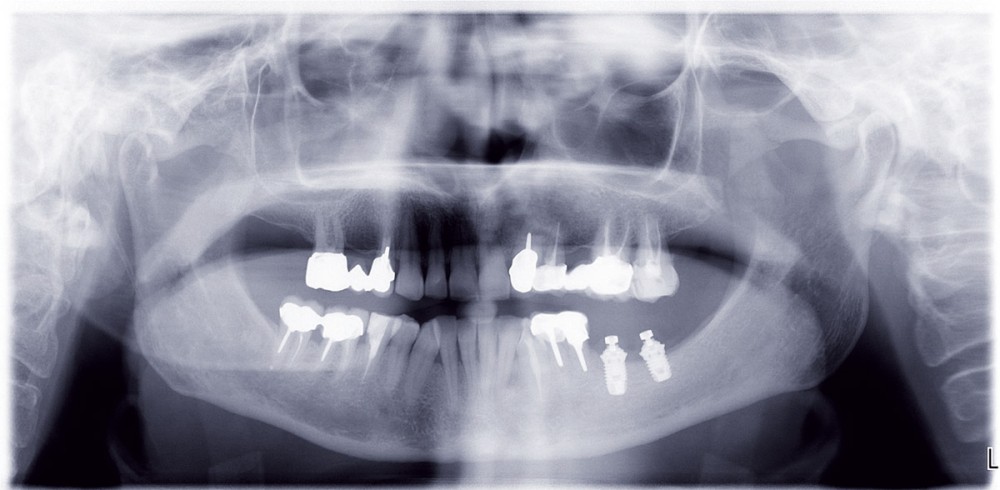

La réhabilitation des secteurs postérieurs maxillaires et mandibulaires résorbés présente un vrai défi lorsque le plan de traitement souhaité implique la pose d’implants [16]. Très souvent, en cas d’insuffisance de volume osseux résiduel, le placement des implants nécessite une intervention d’augmentation osseuse. Cela fait appel à un certain nombre de techniques de chirurgie avancées comme les greffes de sinus, les greffes d’apposition, la distraction et la régénération osseuse guidée.

De nombreuses publications ont décrit la mise en place d’implants courts dans des volumes osseux réduits comme étant une alternative chirurgicale apportant de bons résultats [1, 20]. De ce fait, le recours à de tels implants s’impose comme une solution thérapeutique à considérer avec le plus grand intérêt avant de recourir à une procédure chirurgicale spécifique, souvent lourde et techniquement plus difficile.

La définition du terme « implant court » varie selon les auteurs. Certains considèrent que les implants courts sont ceux de moins de 10 mm [7], alors que d’autres ont considéré comme « court », lors de la première conférence de consensus de l’European Association of Osseointegration (EAO) [14], un implant présentant une longueur intra-osseuse inférieure ou égale à 8 mm.

Dans la région maxillaire postérieure, la question de la greffe de sinus ou du placement d’un implant court peut se poser en présence d’une hauteur osseuse…